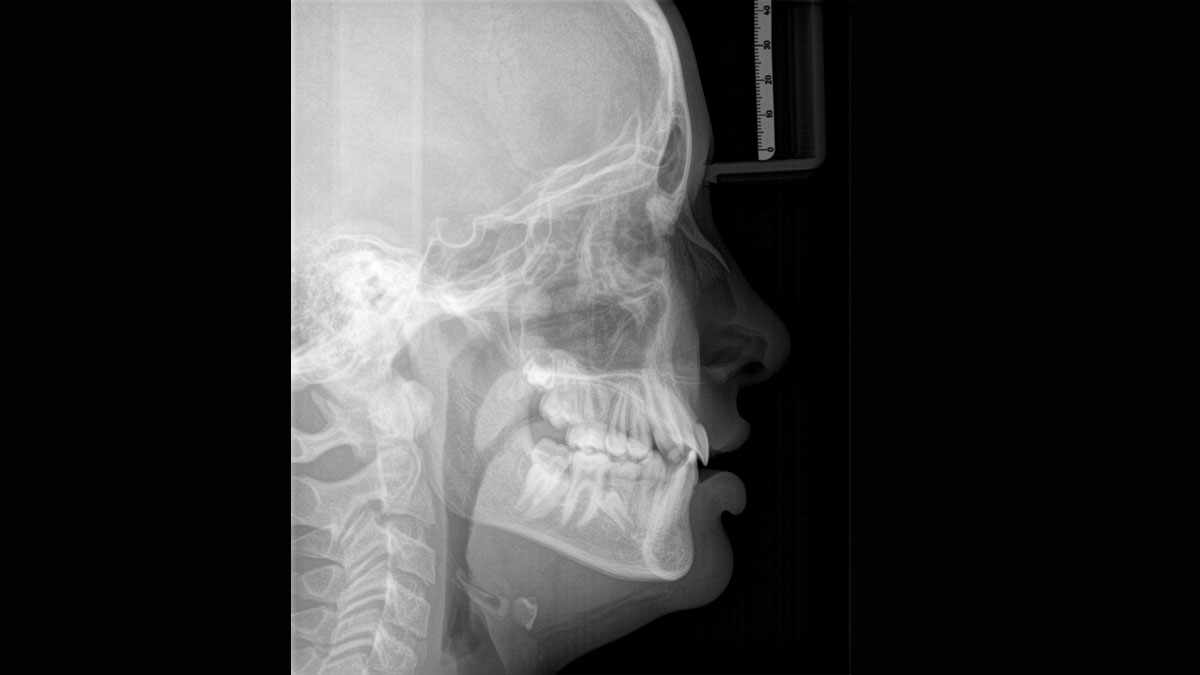

For exceptional panoramic images with high sharpness. You can choose an optional right or left cephalometric arm, which can be retrofitted at any time